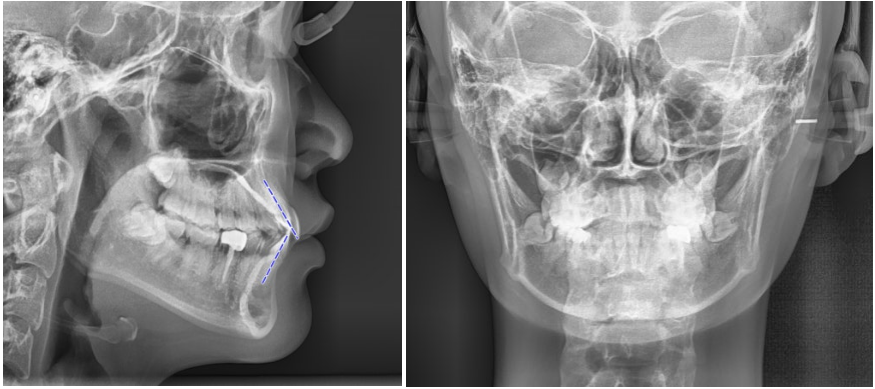

정밀한 검사를 위해

엑스레이를 비롯한 치근단 엑스레이,

턱관절 검사를 통해

치아 교정을 하여도

괜찮은지 확인하는 과정을 걸쳤습니다.

이와 같이 정밀한 검사를 걸친 뒤

위 사항을 종합적으로 고려하여